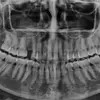

Mesleki ilgi alanları "estetik diş hekimliği" ve "cerrahi uygulamalar" olup

butik dişhekimliği anlayışıyla kişiye özel gülüş tasarımları üzerinde çalışarak uygulamalar yapmaktadır.